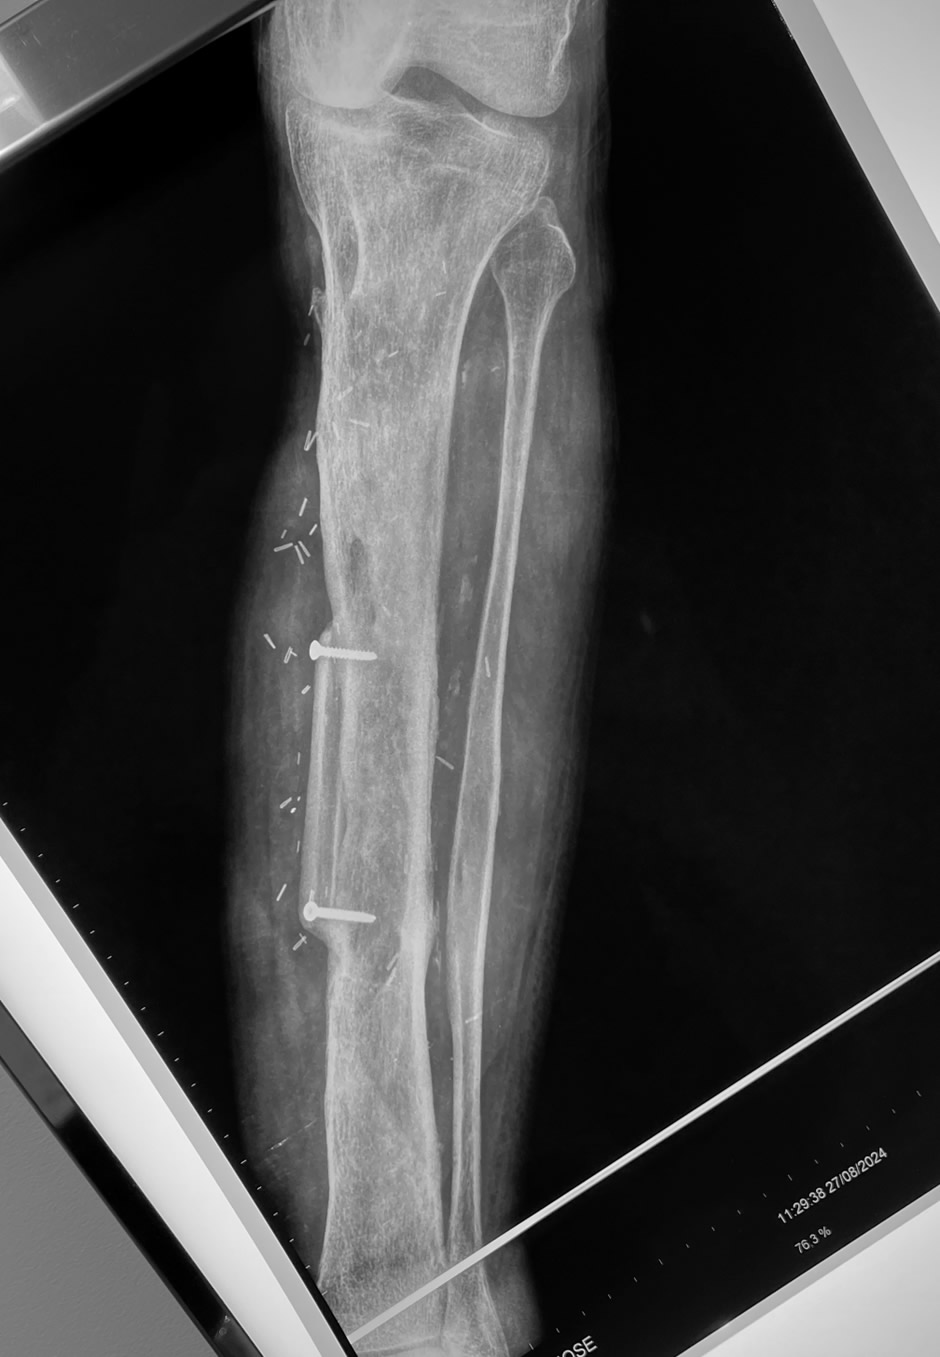

Paso 2: Reconstrucción de la fractura de tibia residual

Se reconstruyó el volumen óseo en la zona fracturada mediante un colgajo de peroné contralateral para reforzar la tibia residual.

Paso 3: Retirada del fijador externo y carga de peso

Tres meses después de la reconstrucción ósea se retiró el fijador externo y el paciente comenzó a cargar peso progresivamente.